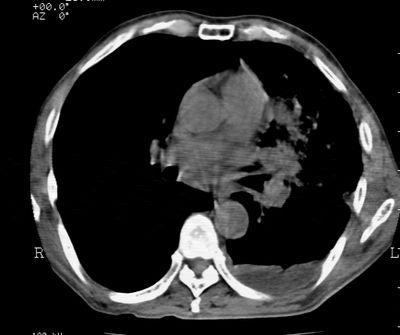

标题: CT24000:M65,胸痛,胸闷月余,既往慢支,肺气肿,肺心病 [打印本页]

标题: CT24000:M65,胸痛,胸闷月余,既往慢支,肺气肿,肺心病

左肺门肿块,相应支气管闭塞,左肺上叶、舌叶大片及散在高密度影,部分呈不张改变,两肺纹粗乱,左侧胸腔积液。考虑左侧中央型肺癌伴阻塞性改变。

左肺门见巨大软组织肿块影,直径约--,境界清,左上肺叶支气管变窄,左上肺舌叶见大片状密实影,余肺纹理增多、紊乱、纤细、部分网格状,两肺透亮度增高,纵隔内见增大多发淋巴结影,心影略左偏,左侧少量胸腔积液。

左侧中央型肺癌伴左上肺舌叶不张、纵隔淋巴结转移,左侧少量胸腔积液。